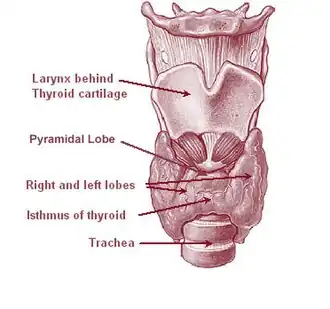

The thyroid gland is a butterfly-shaped organ composed of two lobes, left and right, connected by a narrow tissue band, called an "isthmus".[4] It weighs 25 grams in adults, with each lobe being about 5 cm long, 3 cm wide, and 2 cm thick and the isthmus about 1.25 cm in height and width.[4] The gland is usually larger in women than in men, and increases in size during pregnancy.[4][5]

The thyroid is near the front of the neck, lying against and around the front of the larynx and trachea.[4] The thyroid cartilage and cricoid cartilage lie just above the gland, below the Adam's apple. The isthmus extends from the second to third rings of the trachea, with the uppermost part of the lobes extending to the thyroid cartilage and the lowermost around the fourth to sixth tracheal rings.[6] The infrahyoid muscles lie in front of the gland and the sternocleidomastoid muscle to the side.[7] Behind the outer wings of the thyroid lie the two carotid arteries. The trachea, larynx, lower pharynx and esophagus all lie behind the thyroid.[5] In this region, the recurrent laryngeal nerve[8] and the inferior thyroid artery pass next to or in the ligament.[9] Typically, four parathyroid glands, two on each side, lie on each side between the two layers of the thyroid capsule, at the back of the thyroid lobes.[4]

Sometimes there is a third lobe present called the pyramidal lobe.[5] When present, this lobe often stretches up to the hyoid bone from the thyroid isthmus and may be one to several divided lobes.[4] The presence of this lobe ranges in reported studies from 18.3%[11] to 44.6%.[12] It was shown to more often arise from the left side and occasionally separated.[11] The pyramidal lobe is also known as Lalouette's pyramid.[13] The pyramidal lobe is a remnant of the thyroglossal duct, which usually wastes away during the thyroid gland's descent.[5] Small accessory thyroid glands may in fact occur anywhere along the thyroglossal duct, from the foramen cecum of the tongue to the position of the thyroid in the adult.[4] A small horn at the back of the thyroid lobes, usually close to the recurrent laryngeal nerve and the inferior thyroid artery, is called Zuckerkandl's tubercle.[9]